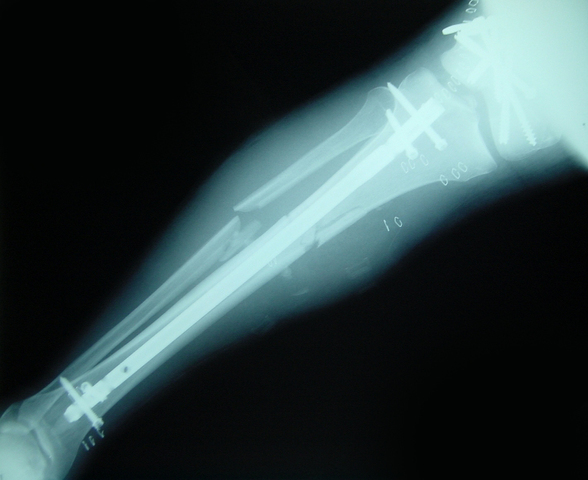

• Lochie Broke his leg

Lochie Broke his leg

My family and I went on a holiday to Queensland so we could go to the theme parks like Wet 'n' Wild, Movie World, Dream World and White 'n' Water World. We got off the plane and headed to our hotel to drop our bags and relax before the big day tomorrow at the theme parks. Me and my sister were jumping off the bunk beds to the king that my Mum and Dad were sleeping for fun. My sister said I'll push you because it was funner that way and I wasn't ready so I feel flat onto the floor screaming.